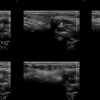

Draw in the second image below where the fillers are located. To check if your answer is correct, swipe the first image to the right.